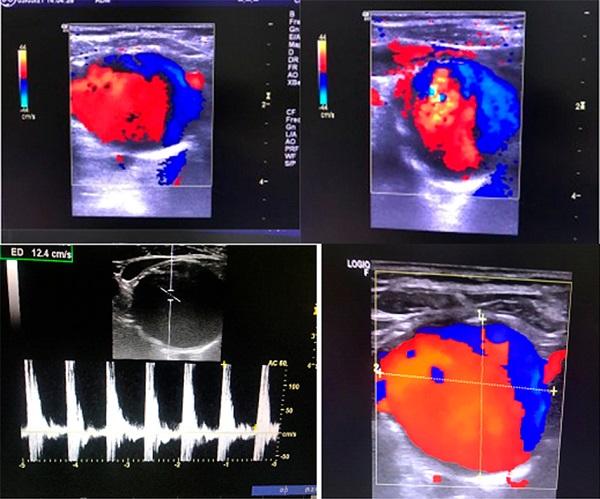

El examen físico demostró una masa pulsátil a nivel supraesternal derecho, y un soplo sistodiastólico en dicho nivel. La ecografía vascular reveló un aneurisma del TBC de 35 × 28 mm, y la presencia de placas fibrolipídicas hiperecogénicas, sin obstrucciones significativas. No se observaron dilataciones aneurismáticas en los otros vasos del cuello explorados. Se realizó un ecocardiograma que no demostró dilatación aórtica y sí una ligera elongación supravalvular de 33 mm (Figura 1). El Doppler color (Figura. 2) demostró efecto Yin Yang que rellenaba el aneurisma. Se estudiaron también las arterias de ambos miembros superiores e inferiores, no registrándose dilataciones aneurismáticas. Con este antecedente, se decidió solicitar laboratorio de rutina, hormonas tiroideas, glucemia, Hb A1C, VDRL. Como tratamiento médico se indicaron antiagregantes plaquetarios y rosuvastatina 20 mg/día. La paciente fue derivada a cirugía vascular para evaluar tratamiento quirúrgico o endovascular, intercurre con una neumopatía de la comunidad por lo cual debió ser internada, con buena respuesta al tratamiento con antibióticos. A su alta y luego de ateneo se decidió operarla del aneurisma, actualmente permanece en lista de espera para cirugía.